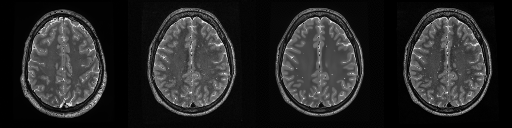

HCP T2w dataset

We utilize images from the publicly available Human Connectome Project (HCP) [51] T2-weighted (T2w) images dataset for the task of compressed sensing, which contains brain images from 47 patients. The HCP dataset includes cross-sectional images of the brain taken at different levels and angles.

Compressed sensing

We train a flow-based model from scratch on 10,000 randomly sampled images, utilizing the ncsnpp architecture [9] with minor adaptations for grayscale images. We employ compression rates , meaning . The measurement operator is given by a subsampled Fourier matrix, whose sign patterns are randomly selected. We evaluate our reconstruction algorithm’s performance on 200 randomly sampled test images.

We present the quantitative and qualitative results of compressed sensing in Tab. 1 and Fig. 4, respectively. As shown in Tab. 1, our method consistently achieves the best performance across varying compression rates . In Fig. 4, our method produces reconstructions that are more faithful to the original images, with fewer artifacts, leading to higher accuracy and clearer details.